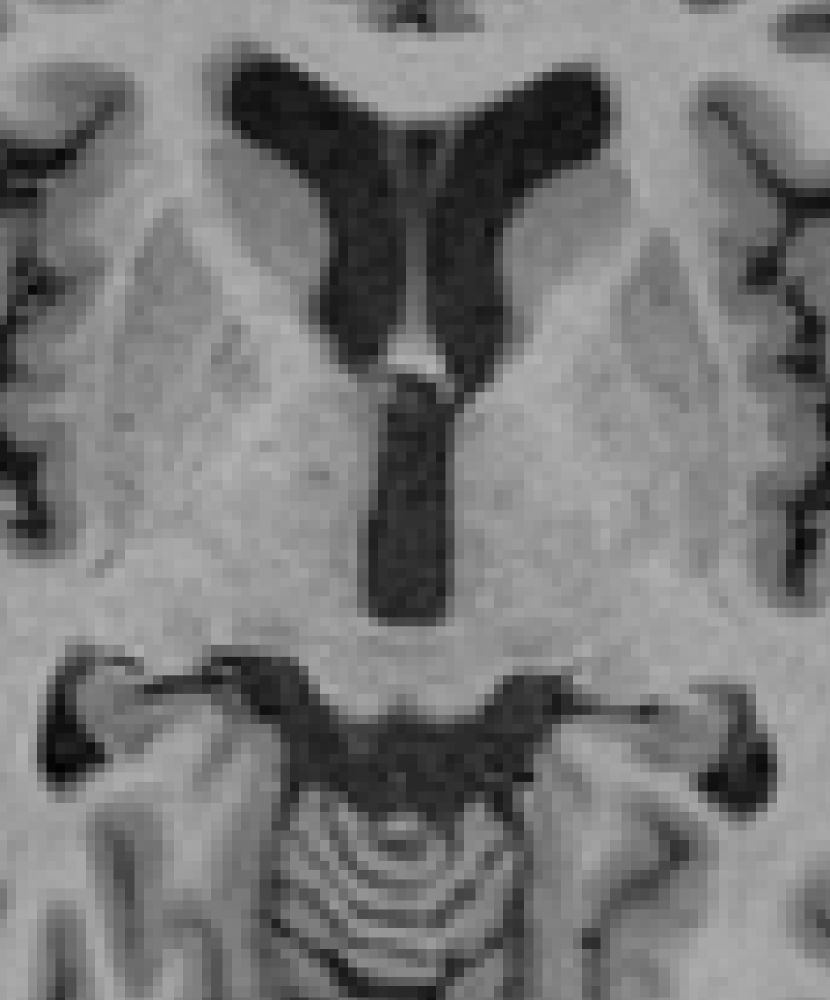

3.4 Post-processing

Contrast-driven post-processing techniques may lead to unexpected/unsatisfactory smoothing results. For instance, sub-cortical structures and some parts of the brainstem could be shrunk in this step due to low contrast with surrounding areas as shown in Fig. 7. However, this does not signify that the method is not capable of refining the segmentation since both the intensity features and the prior probabilities take part in the process.

Refer to caption

(a)

(b)

(c)

(d)

Figure 7: Two input slices in which low contrast between the region of interest and the surrounding areas is exhibited. In the image (a) the focus is on the mesencephalon which is highlighted by the purple area in (b). In (c) the focus is on caudate, putamen, pallidum and thalamus structures presented in green in (d).